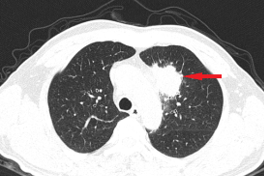

Từ 1 điểm dị thường ở cổ, người đàn ông 35 tuổi phát hiện ung thư di căn

Người đàn ông cho rằng hạch nhỏ ở cổ là biểu hiện cảm cúm nhưng khi đi khám, bác sĩ đã xác định đó là ung thư di căn.